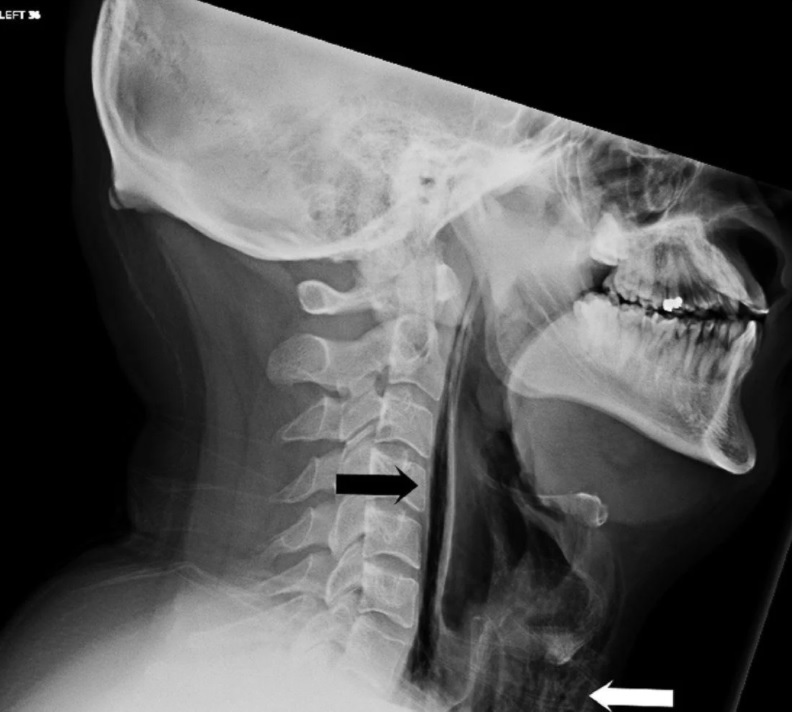

En un estudio publicado por British Medical Journal Case Reports, los doctores describen su confusión inicial cuando el paciente llegó a la sala de emergencias del hospital de Leicester quejándose de tener dificultades para deglutir y “una sensación de taponazos” en su inflamado cuello.

El paciente de 34 años dijo a los doctores que sus problemas comenzaron después que trató de impedir un estornudo tapándose la nariz y la boca. Eventualmente perdió la voz y pasó una semana en el hospital.